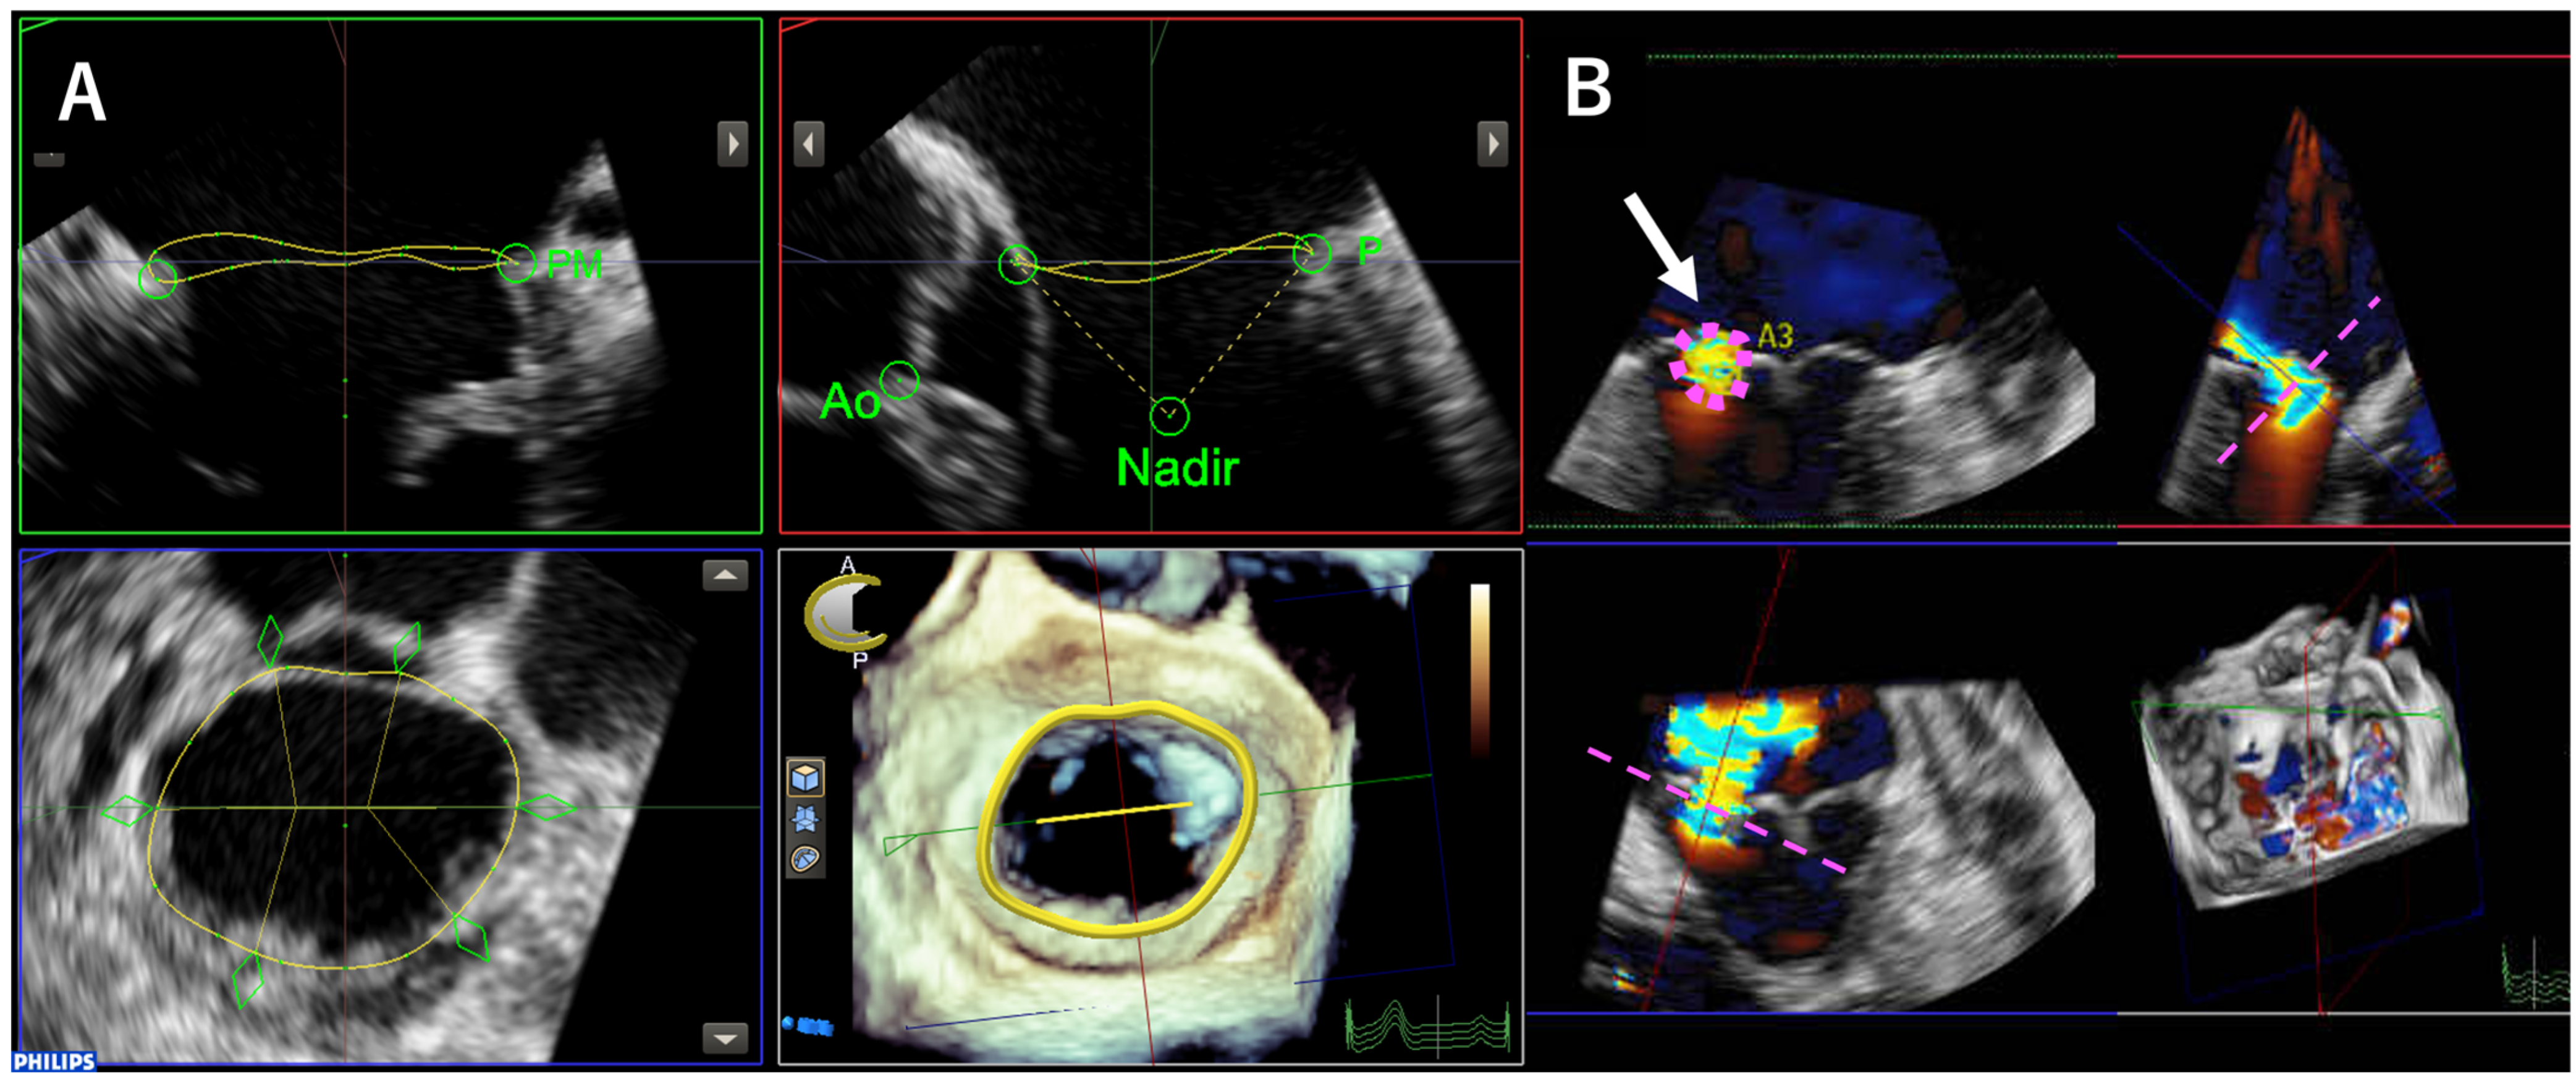

2.2. Transesophageal Echocardiography